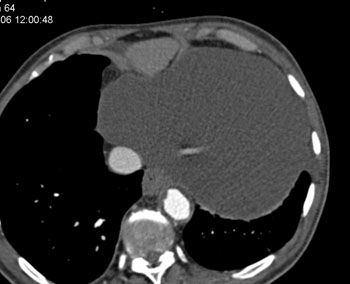

Question 5: 47 year old male with mass discovered on CT during chest pain workup. What is the diagnosis?

Diagnosis: Pericardial cyst

• Usually at right anterior costophrenic angle

• Water density on CT

• 2-30 cm in size

• Homogeneous without any enhancement

• Anomalous outpouching of the parietal pericardium

• Right costophrenic location in 70-90% of cases

• Size from 1 cm to >25 cm

• Usually incidental finding in an asymptomatic person

• Smoothly marginated lesion surface

• Less than 10 HU

• No enhancement on contrast studies

• Size range from 2-30 cm